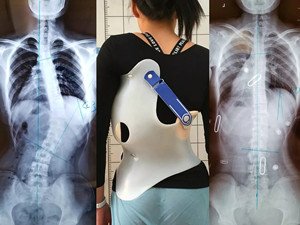

脊柱側(cè)彎是指脊柱的一個或數(shù)個節(jié)段向側(cè)方彎曲,并伴有椎體旋轉(zhuǎn)的三維脊柱畸形。

該病如不及時發(fā)現(xiàn)、及時治療,可發(fā)展成非常嚴重的畸形,并影響心肺功能,嚴重者甚至導(dǎo)致癱瘓。對此病的嚴重性認識不夠,會造成脊柱側(cè)彎患者的終身遺憾!

在青少年快速發(fā)育期內(nèi),身體長得越快,脊柱側(cè)彎的進展就越快。矯形支具通過長時的反向矯正力將脊柱維持在一個矯正的狀態(tài);然而由于長時間地佩戴支具會導(dǎo)致肌肉萎縮,當支具摘除,脊柱側(cè)彎回彈,且患者無法形成成自我矯正力,呼吸功能亦無法得到改善。最好是在穿戴支具的同時,配合體操訓(xùn)練,通過一系列矯正動作以及呼吸訓(xùn)練,平衡肌力,兩者結(jié)合不但可以穩(wěn)定脊柱,且能增加改善機會。